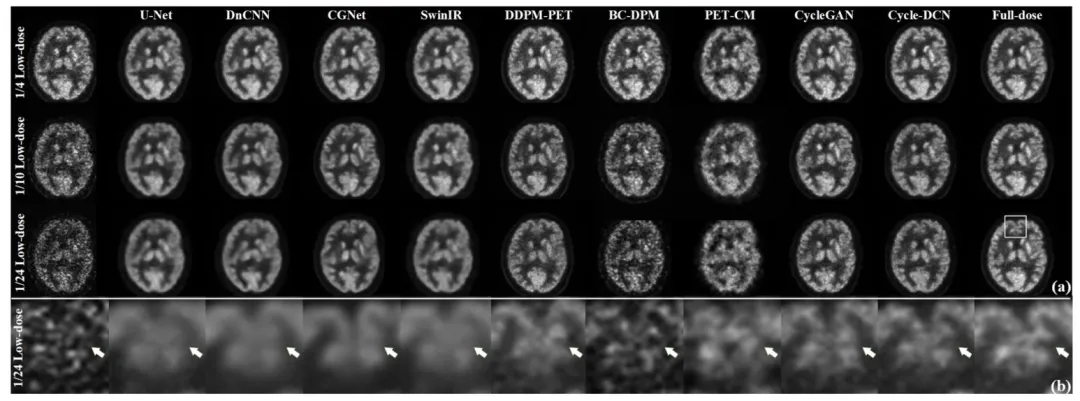

The proposed Cycle-DCN model was systematically compared with several established image denoising and restoration methods, including widely used U-Net, classic denoising model DnCNN (Zhang et al., 2017), the more recent image restoration model CGNet (Ghasemabadi et al., 2024), the Swin Transformer-based SwinIR, CycleGAN, and three diffusion-based approaches: DDPM-PET, PET-CM, and BC-DPM. Table 1provides the quantitative results, showing the mean, standard deviation, and statistical significance based on paired t-tests for each evaluation metric. Fig. 4(a) presents a visual comparison of a representative slice across the nine models, along with the corresponding full-dose and low-dose images at three different dose levels.For ¼ low-dose images, the PSNR, SSIM, and NRMSE metrics are comparable across all evaluated models. While DnCNN and SwinIR slightly outperforms Cycle-DCN in some measures, these differences are not statistically significant (p > 0.05). In contrast, for the more challenging 1/24 low-dose images, Cycle-DCN achieves superior metric values. The three diffusion-based methods—DDPM-PET, PET-CM, and BC-DPM—consistently yielded inferior performance under all the three low-dose conditions. As shown in Fig. 4(a), U-Net and DnCNN result in excessive smoothing, leading to increased deviation from the full-dose images at lower dose levels, with small sulci becoming nearly indistinguishable. However, Cycle-DCN remains closer to the full-dose images, demonstrating better robustness. In the enlarged views in Fig. 4(b), Cycle-DCN uniquely preserves brain structures such as sulci and gyri, producing visual outputs more consistent with full-dose images compared to other models. Among the three diffusion-based methods, DDPM-PET produced visually promising results across all dose levels. However, the performance of BC-DPM (trained unconditionally) and PET-CM (with two-step sampling) deteriorated rapidly as the dose decreased, resulting in significantly degraded image quality.

4.1 定量评估 4.1.1 峰值信噪比(PSNR)、结构相似性指数(SSIM)及归一化均方根误差(NRMSE)对比 将所提Cycle-DCN模型与多种已有的图像去噪和恢复方法进行了系统对比,包括广泛使用的U-Net、经典去噪模型DnCNN(Zhang等,2017)、较新的图像恢复模型CGNet(Ghasemabadi等,2024)、基于Swin Transformer的SwinIR、CycleGAN,以及三种基于扩散的方法(DDPM-PET、PET-CM和BC-DPM)。表1给出了定量结果,包括各评估指标的均值、标准差以及基于配对t检验的统计显著性。图4(a)展示了九种模型在三个不同剂量水平下,代表性切片的视觉对比,同时呈现了对应的全剂量和低剂量图像。 对于¼低剂量图像,所有评估模型的PSNR、SSIM和NRMSE指标表现相当。尽管DnCNN和SwinIR在部分指标上略优于Cycle-DCN,但这些差异无统计学意义(p > 0.05)。相比之下,在更具挑战性的1/24低剂量图像中,Cycle-DCN取得了更优的指标值。三种基于扩散的方法(DDPM-PET、PET-CM和BC-DPM)在所有三个低剂量条件下均表现出持续劣势。如图4(a)所示,U-Net和DnCNN存在过度平滑问题,导致在低剂量水平下与全剂量图像的偏差增大,细小脑沟几乎无法区分。而Cycle-DCN始终更接近全剂量图像,展现出更强的鲁棒性。在图4(b)的放大视图中,Cycle-DCN独特地保留了脑沟、脑回等脑部结构,生成的视觉结果比其他模型更接近全剂量图像。在三种基于扩散的方法中,DDPM-PET在所有剂量水平下均产生了视觉上较理想的结果,但无监督训练的BC-DPM和两步采样的PET-CM的性能随剂量降低迅速下降,导致图像质量显著退化。

Fig. 4. (a) Denoised images from various models at three different low-dose levels for a representative case; (b) The partially enlarged sections of 1/24 low-dose images, showcasing detailed visual comparisons across models.

图4 (a) 代表性病例在三种不同低剂量水平下,各模型的去噪图像;(b) 1/24低剂量图像的局部放大图,展示各模型间的细节视觉对比。